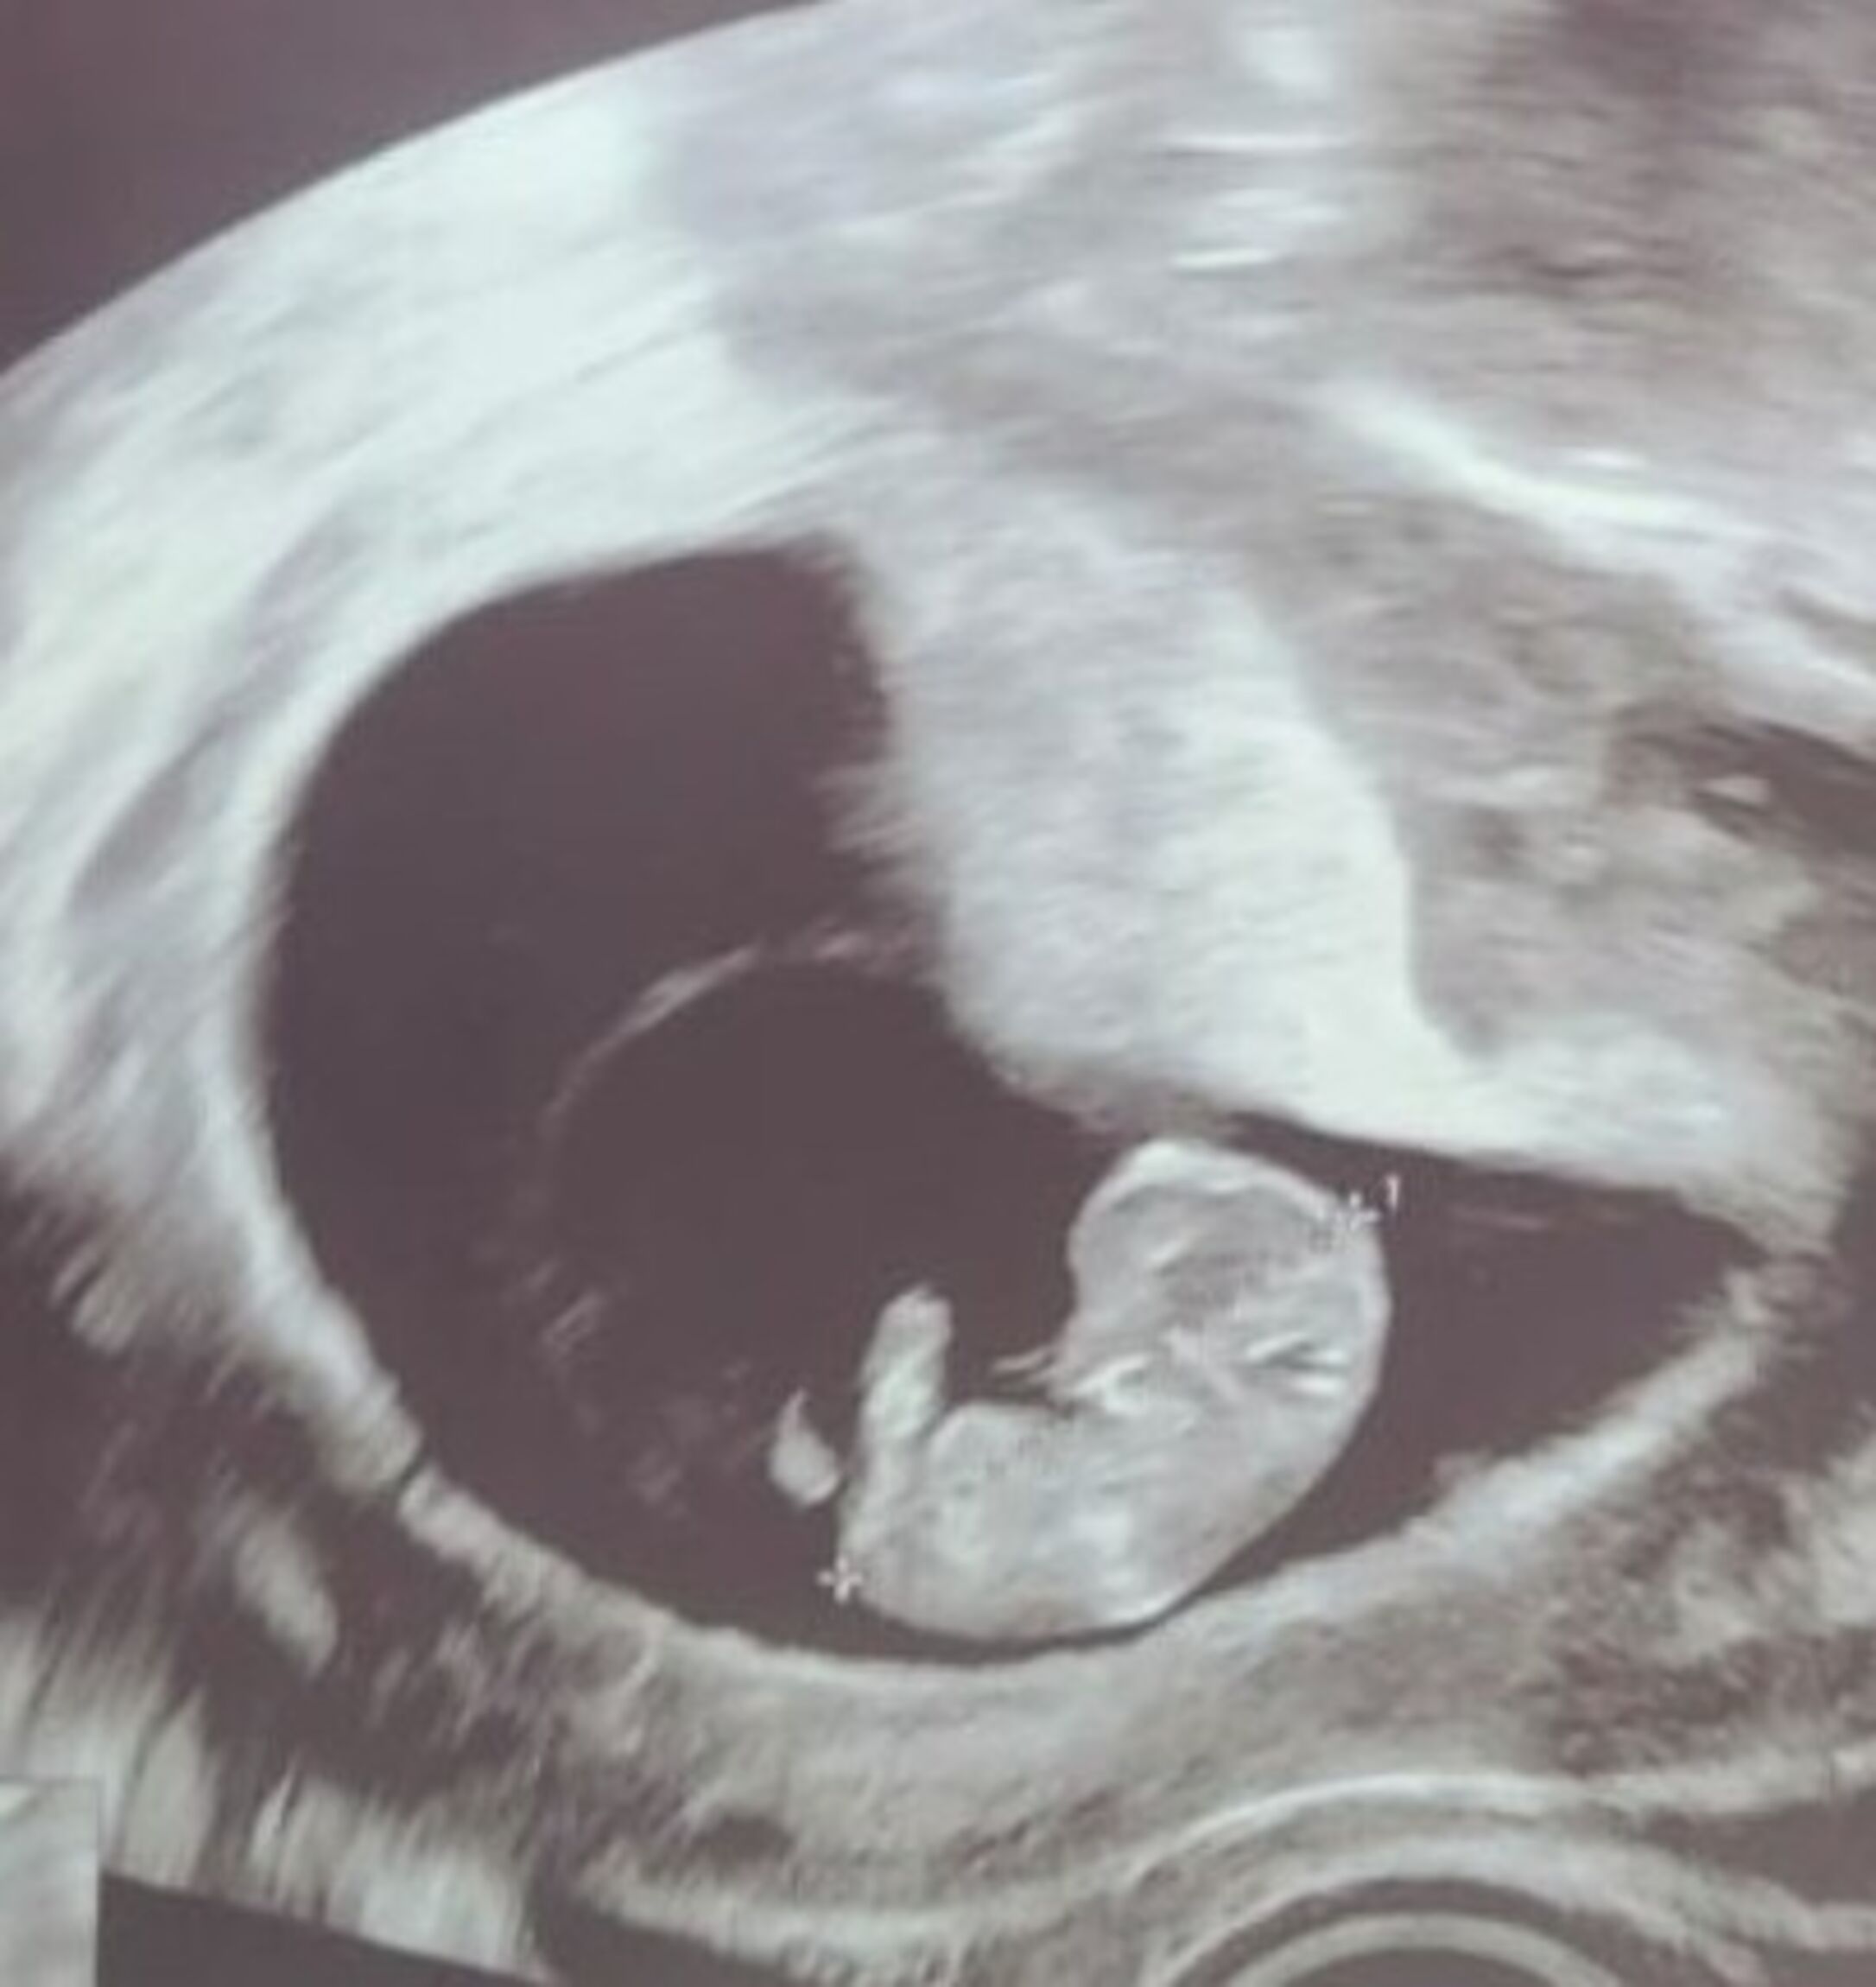

Eine Schwangerschaft ist oft ein Wechselbad der Gefühle - besonders wenn zusätzliche Untersuchungen anstehen oder auf Laborergebnisse gewartet werden muss, kann es sein, dass die Angst überhandnimmt. Dann tut es gut, mit seinen Gedanken nicht allen zu sein.

Wir unterstützen Sie vor Inanspruchnahme von Pränataldiagnostik durch Information und Aufklärung.

Während des Wartens auf den Befund und beraten nach einem auffälligen Befund, damit Sie sich einer Entscheidung annähern können, die für Ihre persönliche Lebenssituation lebbar ist.